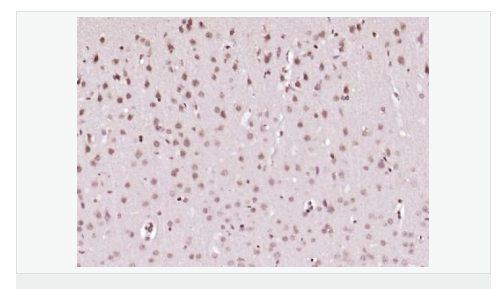

| 產(chǎn)品應(yīng)用 | ELISA=1:5000-10000 IHC-P=1:100-500 IHC-F=1:100-500 IF=1:100-500 (石蠟切片需做抗原修復(fù)) not yet tested in other applications. optimal dilutions/concentrations should be determined by the end user. |